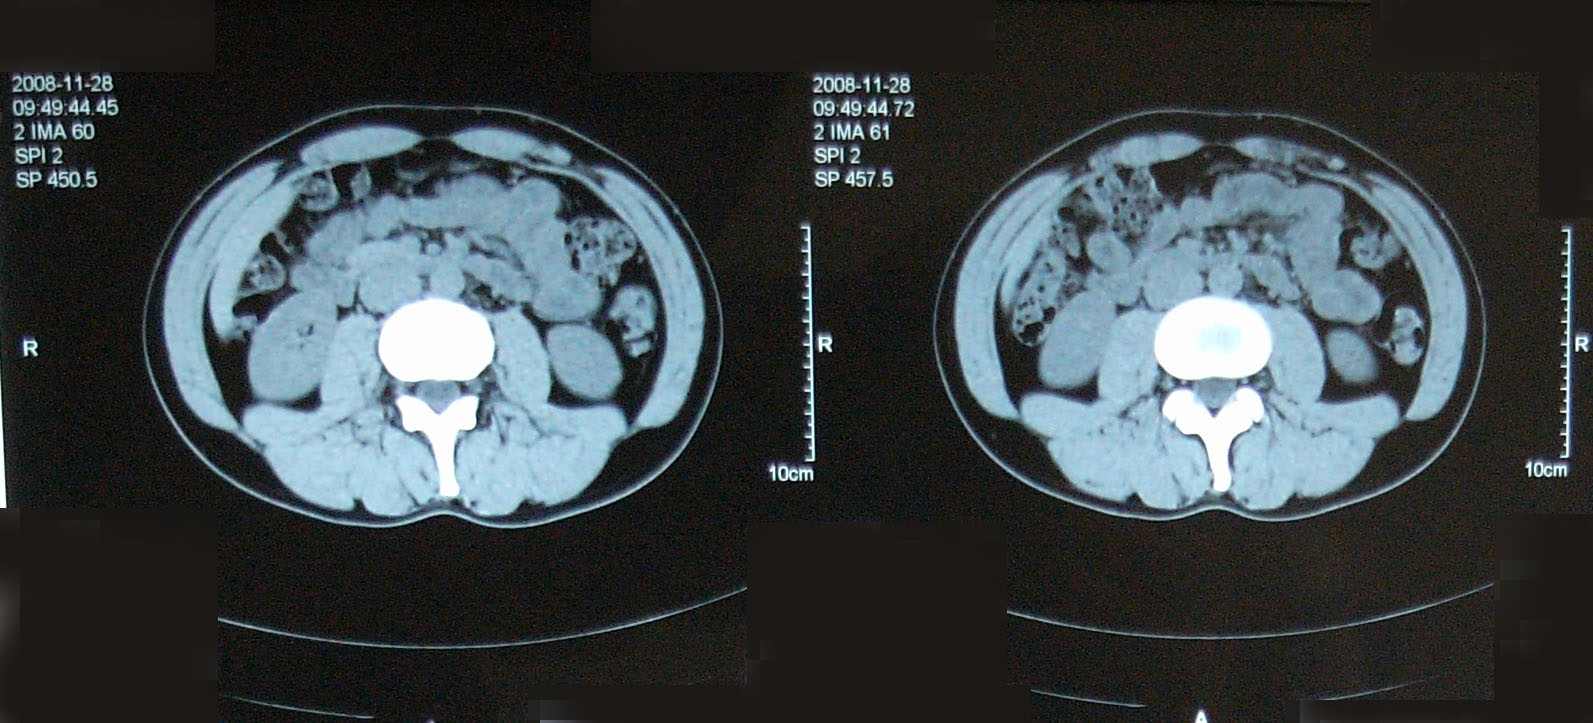

【単純CT】

問題なし! 【腫瘍マーカー】 HCGβ:<0.1 問題なし! 次は9月!

問題なし! 【腫瘍マーカー】 HCGβ:<0.1 問題なし! 先週検査でした。 今日はその結果。 今日は珍しく先生が寝ぼけていました(笑)。 次回のレントゲン検査の受付票を何回も出し間違えた。 1回目:診察後清算も済み帰ろうとした所で俺が気がついた。「これ、画像データCDR作成申込書じゃん・・・」 2回目:受付で上記を伝え、看護婦さん:「すいませ~ん!これで大丈夫ですか?」 確認すると今度はXP検査受付票なので「OKです!ありがとうござ・・・ん?!?これ検査日が今日です・・・・」 看護婦さんダッシュで戻っていきました。 3回目:看護婦さん:「今度は~~」 俺:「間違いないです!」 看護婦さん:「先生寝ぼけてるんですよぉ~」 次は3月!

【CT画像】

単純CT:特に変化を認めず。 【腫瘍マーカー】 HCGβ:<0.1 問題なしでした! 今日は画像はありません。 理由は、病院側でデジタル化が進んでいて、PCモニターでの画像確認となったからです。 今日はフィルムも用意されませんでした・・・・。 先生曰く、そのうちフィルムもなくなるだろうと。 そのときにはCD-R等に焼く対応もするようになっているはずだと。 早くデータで画像がほしい。その時はたくさんアップしますw。 次回は2月です。

今回からCTの造影剤はありませんでした。

勘違いしてた・・・ なので単純CT。 横になって撮るだけなので非常に楽ですね。その分撮影される画像も解像度が低くなりますが・・・ しかし、思えば2005年末頃の単純CTからリンパ転移が疑われ始め、その次からはずっと造影剤を使用したCTだったわけだ。 2008年末の今、やっとそこへ戻ってきたという感じがした。 検査後の帰り、病院の最寄り駅のパン屋で朝食。 改札横に店があるのでガラス越しに行き交う多くの人を眺めながら思う。 2006年の入院中、ヨメも色々思いながらここを通ったんだろう、と。 何ヶ月も。 暑い日も雨の日も。 ただただ「感謝」あるのみです。 本日の検査結果は12/8。